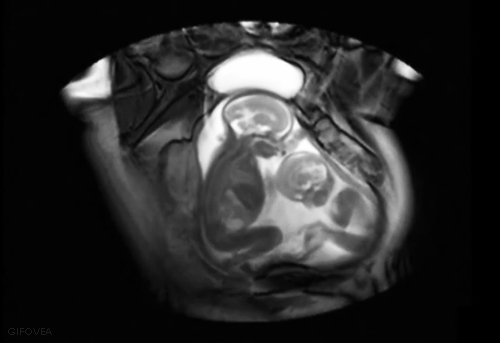

4. Близнецы общаются друг с другом еще будучи эмбрионами

Исследования, проведенные в Университете Падуи, показали, что близнецы общаются и взаимодействуют друг с другом еще в утробе матери, начиная со срока 14 недель гестации.

На 3D-видео, созданных при помощи четырехмерной ультрасонографии, было видно, что в 14 недель плоды протягивали друг к другу руки, а к возрасту 18 недель прикасались друг к другу чаще, чем трогали свое тело, а также жестикулировали друг с другом. Около 30% своего времени они проводили, трогая и поглаживая своего близнеца, при этом так же бережно прикасались к его деликатной области глаз, как и к своей.